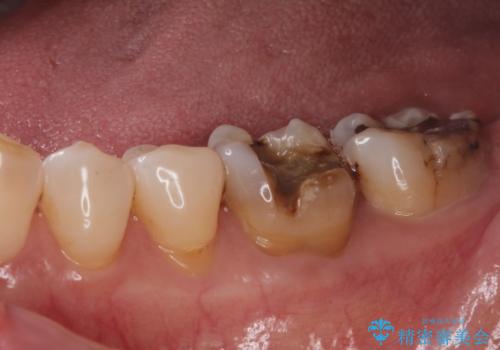

- 奥歯の銀の詰め物が取れたとの事で来院。

詰め物の下に虫歯ができて銀歯が取れてしまった事が予想されます。

白い詰め物でやり直しをしても歯質が薄くなり割れてしまうリスクがあるために、

割れるリスクの少ないジルコニアクラウンにて治療しました。

白い被せ物が入り、とても満足して頂けました。